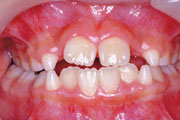

一般矯正の症例

症例4:上顎前突